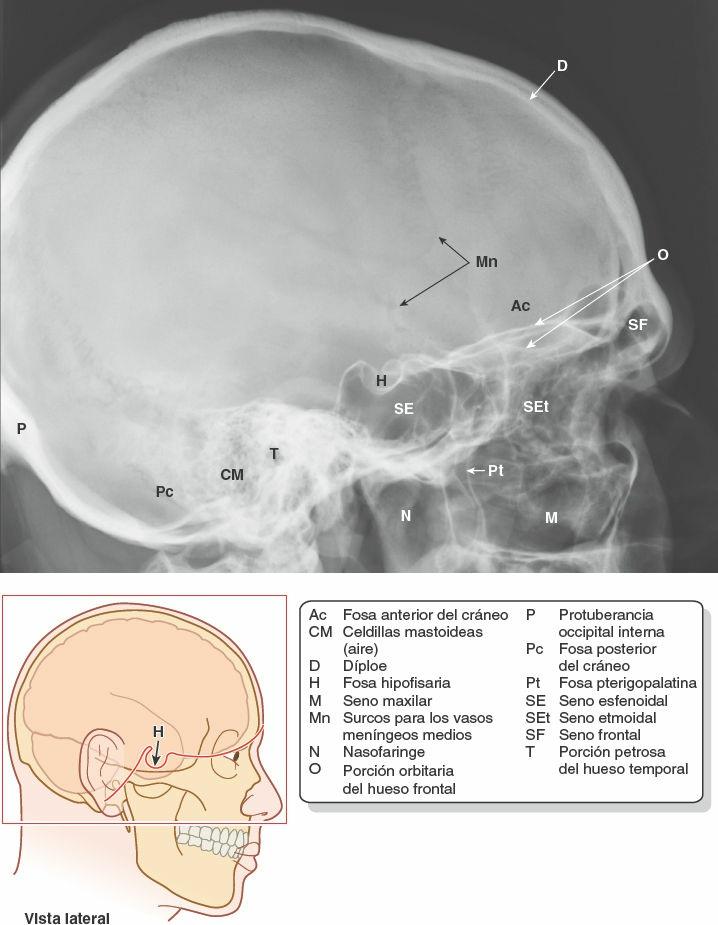

Las paredes de la cavidad craneal varían de grosor en las diferentes regiones. Suelen ser más delgadas en la mujer que en el hombre, y también más delgadas en el niño y el anciano. Los huesos tienden a ser más delgados en las áreas que se hallan bien cubiertas por músculos, como la porción escamosa del hueso temporal (fig. 8-11). Las áreas delgadas de los huesos pueden verse en las radiografías (fig. 8-5) o al sostener un cráneo desecado frente a una luz intensa.

La mayoría de los huesos de la calvaria se componen de las tablas interna y externa de hueso compacto, separadas por el díploe (figs. 8-5 y 8-11). El díploe es hueso esponjoso que contiene médula ósea roja en vida y conductos formados por las venas diploicas. En el cráneo en seco el díploe no es rojo, pues las proteínas se eliminan durante la preparación del cráneo. La tabla interna ósea es más delgada que la externa, y en algunas áreas sólo existe una fina lámina de hueso compacto, sin díploe.